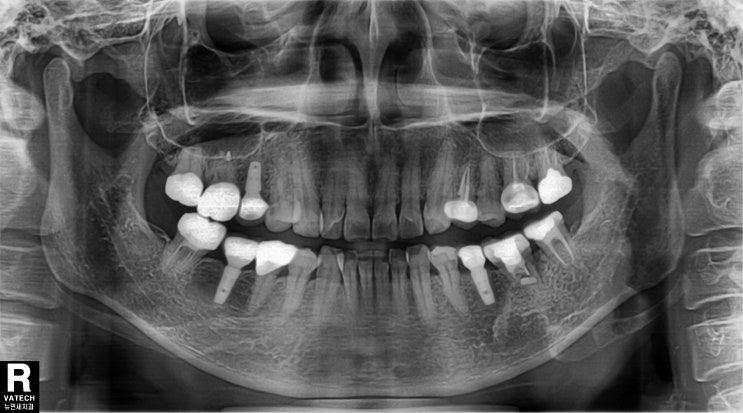

사랑니 자가치아이식 12년 후

임플란트 대신 사랑니 자가치아이식을 시술받은지 12년된 환자분이 오랜만에 내원하셨습니다. 저는 당연히 ...